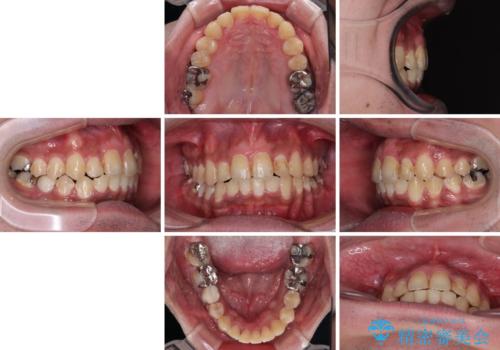

上の前歯が出ているものの、口元が出っ歯というわけではなかったため、非抜歯矯正にて治療を行うこととしました。

下顎に対して上顎歯列が全体的に前方に位置しており、特に右側の奥歯の咬み合わせの前後のズレが大きいため、補助装置を用いて咬み合わせを改善することとしました。

元々むし歯リスクが高かった上に、矯正治療中も磨き残しが多かったため、今後はむし歯治療を行う必要があります。